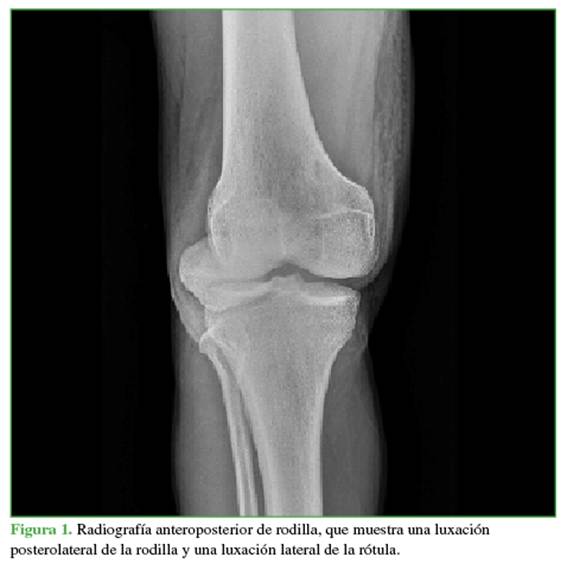

Hombre de 27 años, agricultor y residente en un área rural, sin antecedentes patológicos relevantes. Sufre un accidente de tránsito al caer por un abismo mientras conducía una motocicleta, lo que le provoca un traumatismo en el hombro y la rodilla derechos. Consultó inicialmente en hospital rural, donde le detectaron un gran edema, equimosis y signo del hoyuelo positivo en la rodilla derecha. También, tenía limitación en los arcos de movilidad del hombro y la rodilla. Como no disponían de rayos X, fue derivado a un hospital con servicio de ortopedia. Allí se le tomaron radiografías iniciales (Figuras 1 y 2) y se documentó una fractura diafisaria de húmero que fue inmovilizada con una férula en pinza de azúcar. Además, se diagnosticó una luxación posterolateral de la rodilla y una luxación lateral de la rótula. Dos ortopedistas realizaron tres intentos de reducción bajo sedación (no contaban con anestesia), y lograron reducir la rótula, pero no la rodilla. Se decidió que el paciente requería un centro de trauma para una reducción abierta urgente y descartar una lesión vascular asociada. Se inmovilizó la rodilla con una férula inguinopédica bivalva y fue derivado.

Las radiografías mostraban un aumento del espacio medial debido a la inestabilidad medial. Se ampliaron los estudios con una resonancia magnética (Figuras 4 y 5) para evaluar posibles tejidos o estructuras interpuestos y con una angiotomografía (Figura 6) para descartar una lesión vascular por el tiempo de evolución. Se observó un gran edema en los tejidos mediales, inclusive la cápsula y los tejidos mediales en la zona intercondílea, así como una persistente subluxación de la rodilla. Se descartó un compromiso vascular con integridad del paquete femoropoplíteo.